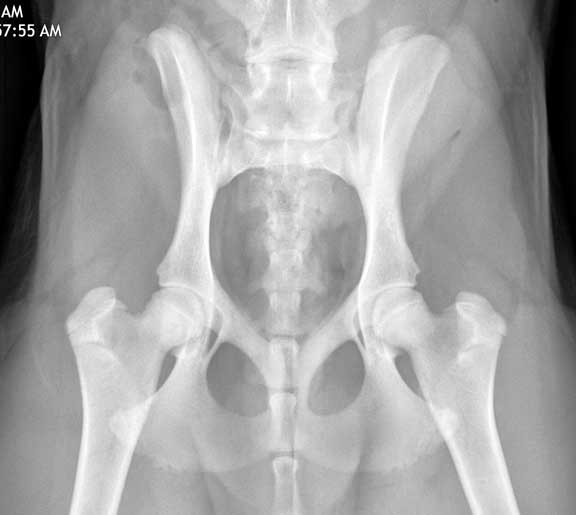

Hip Dysplasia

Labs are susceptible to hip dysplasia, a disease characterized by malformation in the hip socket, which eventually causes arthritis. The symptoms of this disease can vary, from a pet that is just not as active as it should be, to a dog that can barely get up after laying down.

These hips are normal

Our hip dysplasia page has a detailed analysis of this problem that you should learn about if you are contemplating adding a golden to your family.